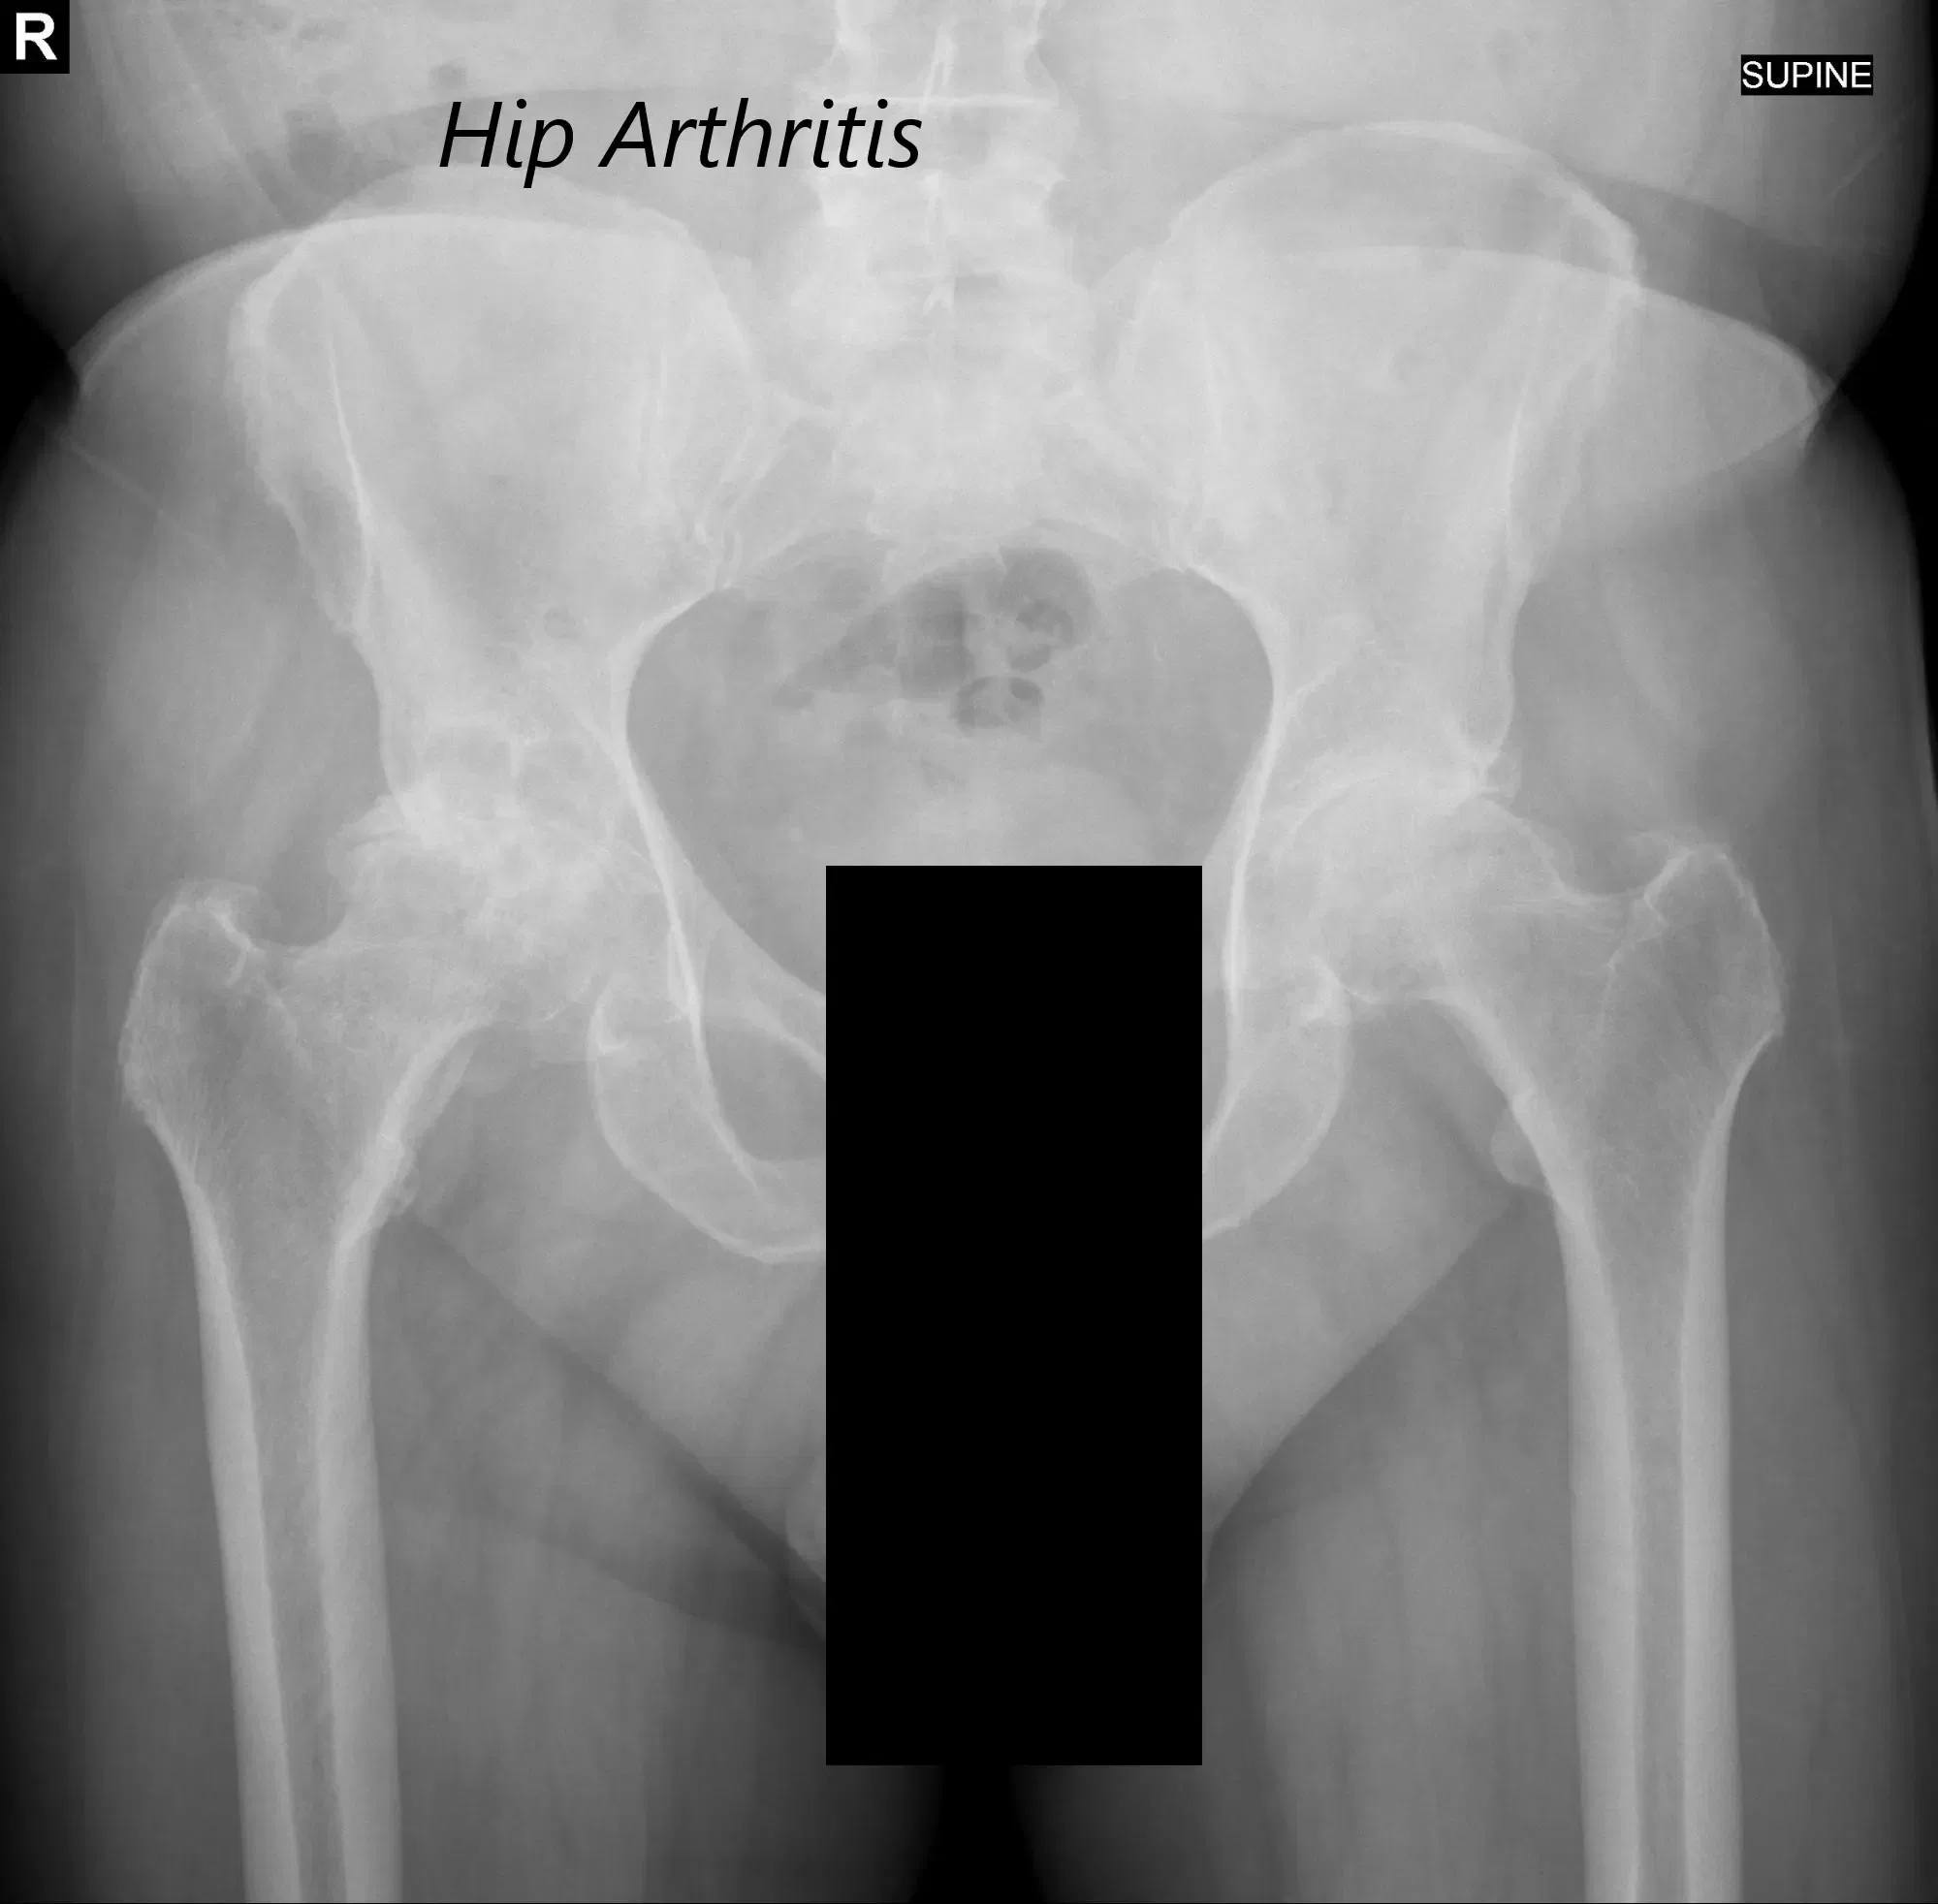

Hubo sensibilidad bilateral en la línea de la articulación anterior de cadera . El triángulo de Bryant digital bilateral fue comparable, lo que sugiere que no hubo acortamiento o alargamiento suprapélvico. Los estudios de imagen revelaron artritis bilateral severa en la cadera.

Vista AP de la radiografía de la pelvis mostrando ambas articulaciones de la cadera con vistas laterales de pata de rana de las articulaciones derecha e izquierda, lo que sugiere una osteoartritis bilateral severa de las articulaciones de la cadera.